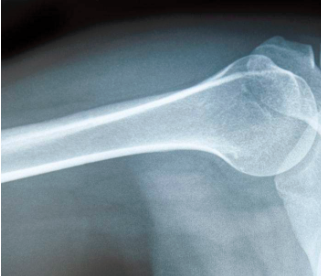

明明追问道:“骨头是不是白色的呢?”妈妈回答道:“对,所以骨折或者骨质增生的辅助检查,首选X光。”